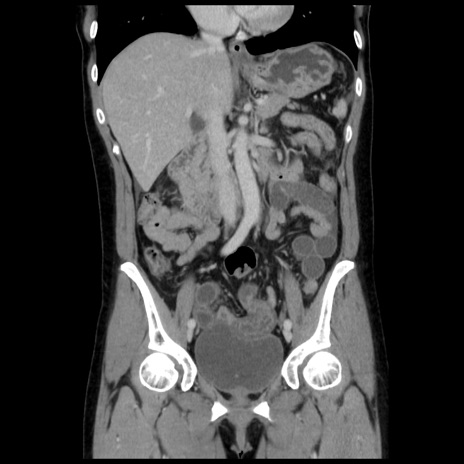

症例10(冠状断像)

【症例】 50歳代女性

【主訴】 腹痛

【現病歴】前日生レバーを食べた。今朝に排便あり。 昼前に突然発症の腹痛を生じ、当院救急外来を受診した。

【既往歴】 子宮筋腫にてで子宮全摘後

【身体所見】 意識清明、腹部:平坦、軟、下腹部やや左を中心に圧痛・反跳痛あり、筋性防御あり

【データ】WBC 7800、CRP 0.07